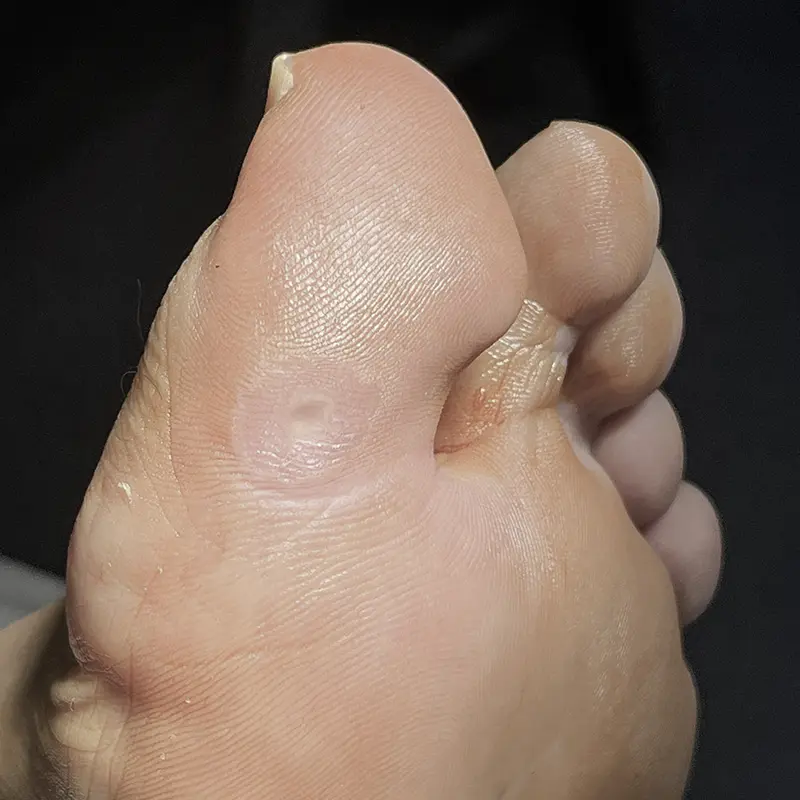

Cirugía de

los dedos y

lesiones locales

Algunas patologías afectan de forma muy localizada, pero no por ello son menos limitantes. Dolor al calzarse, roces constantes o infecciones repetidas suelen ser el motivo de consulta.

Dentro de este grupo se incluyen:

- Cirugía de uñas encarnadas (onicocriptosis).

- Cirugía de helomas (callos) y helomas interdigitales (ojo de gallo).

- Cirugía de partes blandas (quistes, lipomas, úlceras).

- Cirugía de exóstosis y osteocondromas.

- Cirugía de papilomas o verrugas plantares (multipunción, plastias, extirpación).

Son intervenciones que requieren una correcta indicación y un seguimiento adecuado para evitar recidivas y asegurar una buena recuperación.